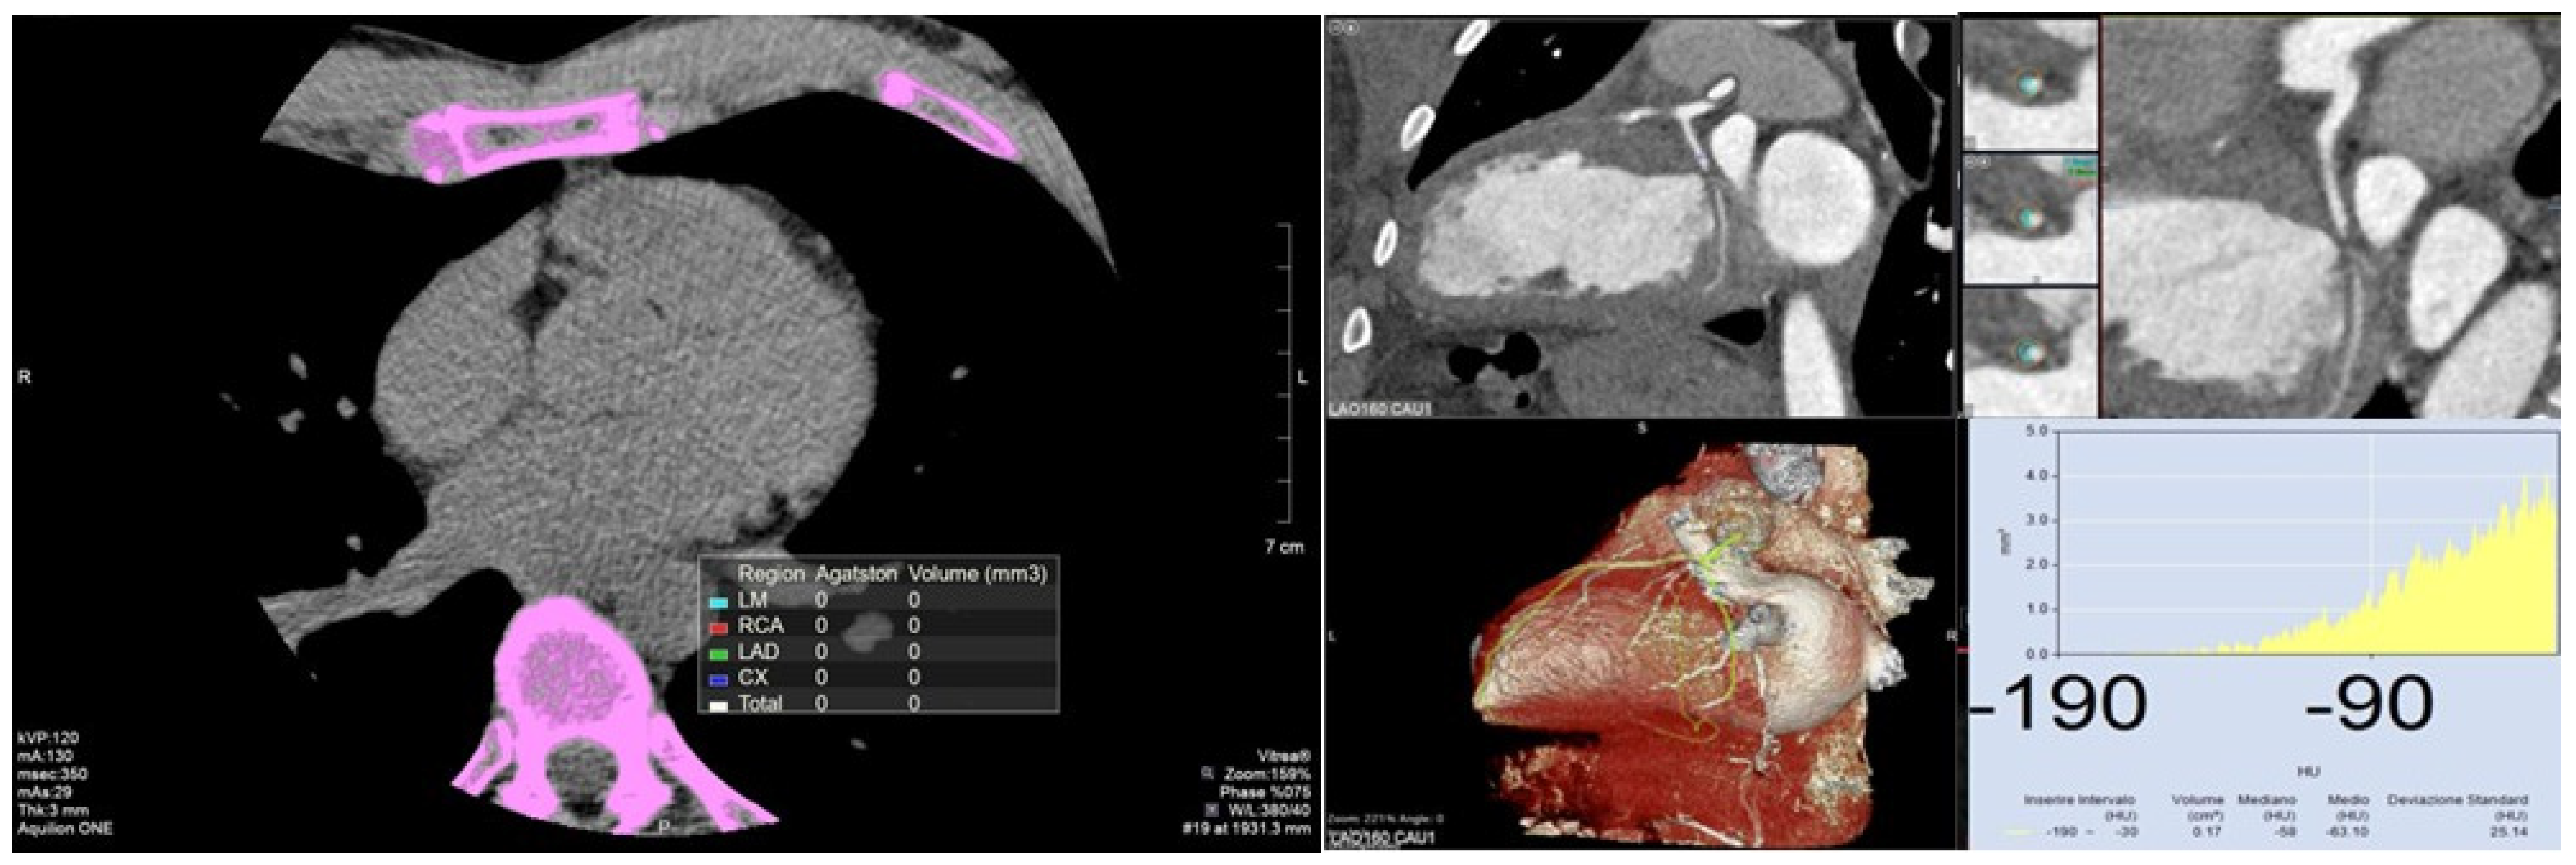

2. Coronary Calcium Score

2.2. Measurement

3. Perivascular Fat Attenuation Index

3.2. Measurement